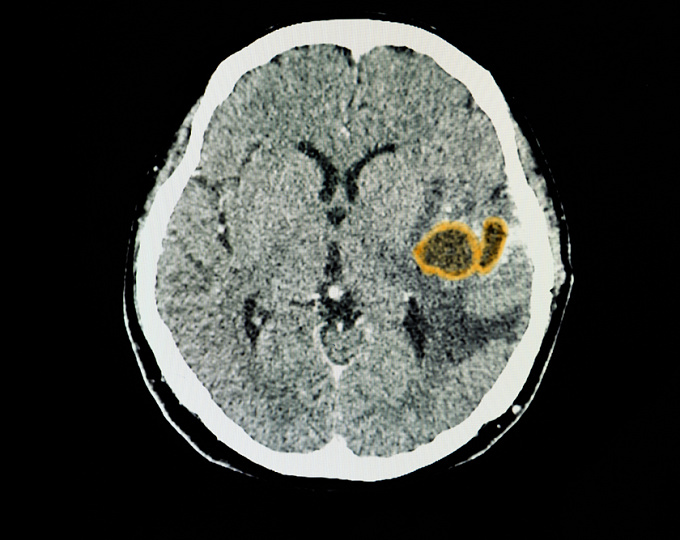

Особенности эпилепсии у пациентов с первичной лиифомой центральной нервной системы

Эпилепсия является часто встречаемся осложнением опухолей головного мозга.

Целью исследования было оценить распространенность, время возникновения и факторы риска эпилепсии у пациентов с первичной лиифомой центральной нервной системы (ЦНС).

• В исследовании приняли участие 330 пациентов, 48% из которых были мужчинами, средний возраст участников исследования составил 68 лет.

• У 25% участников исследования был зафиксирован как минимум один эпизод судорог с момента установления диагноза. У 12% пациентов судороги были диагностированы в дебюте лимфомы, у 5% на изначальном этапе лечения, у 8% пациентов в период прогрессии опухоли и у 2% в период ремиссии.

• Фокальные судороги являлись наиболее частым типом судорог (52% пациентов).

• Противоэпилептическая терапия была эффективна у 98% пациентов.

• Кортикальный контакт (повышение риска в 9 раз; p < 0,001) и высокий пролиферационный индекс (повышение риска в 6 раз; p = 0,02) являлись независимыми факторами риска эпилепсии.

• Пациентов с эпилепсией отличал боле короткий период выживаемости без прогресии опухоли (9,6 vs 14,1 месяцев, p = 0,03) и короткий период выживаемости (17 vs 44,1 месяцев, p = 0,09).

Эпилепсия наблюдается у четверти пациентов с первичной лимфомой ЦНС, у половины пациентов эпилепсия сопровождает первые симптомы заболевания и может быть потенциальным маркером прогрессии заболевания.